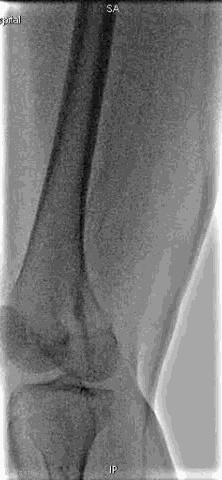

手术过程

抽吸结果